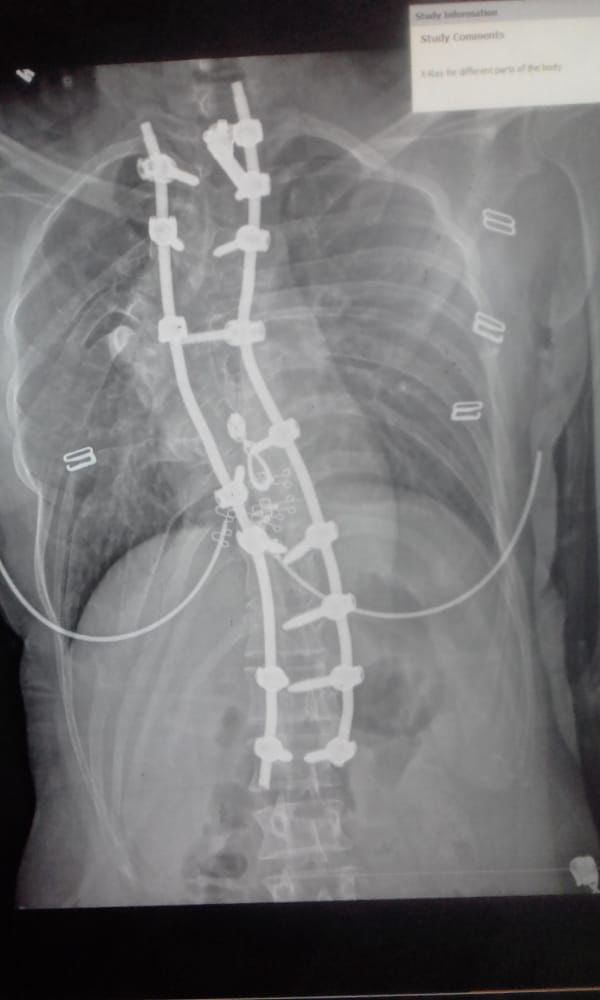

تعرضت فتاة سورية لحادث مأساوي، أصيبت على إثره بإصابات بالغة في العمود الفقري، حيث تعاني من جنف في العمود الظهري نحو الأيمن، والتحام في أجسام الفقرات الظهرية الخامسة والسادسة والسابعة، والتحامات في بعض الأضلاع اليمني.

وأشارت عالية إلى أن الأطباء في سوريا أخبروها بإمكانية علاجها في مصر ونجاح العملية على يد جراح تقويم العظام والعمود الفقري الدكتور هاني عبد الجواد، مشيرة إلى أنها ما زالت تعاني من تشوهات العظام في القفص الصدري الأيمن واحتقان السرتين الرئويتين.